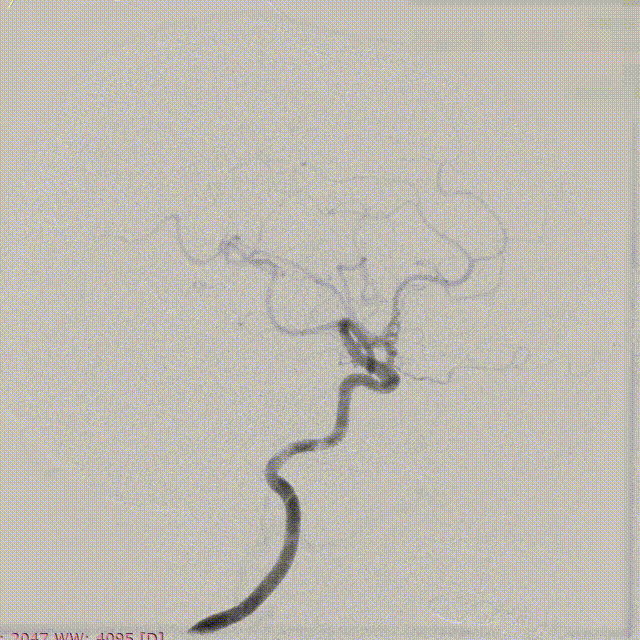

盖延廷教授病例分享一:左侧颈内动脉多发动脉瘤

患者:女性,55岁。

主诉:头疼,检查发现动脉瘤8月余。

入院查体:颅内多发动脉瘤。

术前诊断:

左侧颈内动脉:

远端锚定点脉前起始近端;近端锚定点海绵窦段。

载瘤动脉远端血管直径:3.23 mm

载瘤动脉近端血管直径:4.17 mm

选用4.25mm*25mm 强易达(Choydar)密网支架。

支架及支架微导管到位。

支架头端打开。

支架远端打开造影。

等张释放,支架中段打开至50%释放标记点。

支架中段打开造影。

支架近端打开,完全释放。

支架完全释放造影。

术后即刻造影。